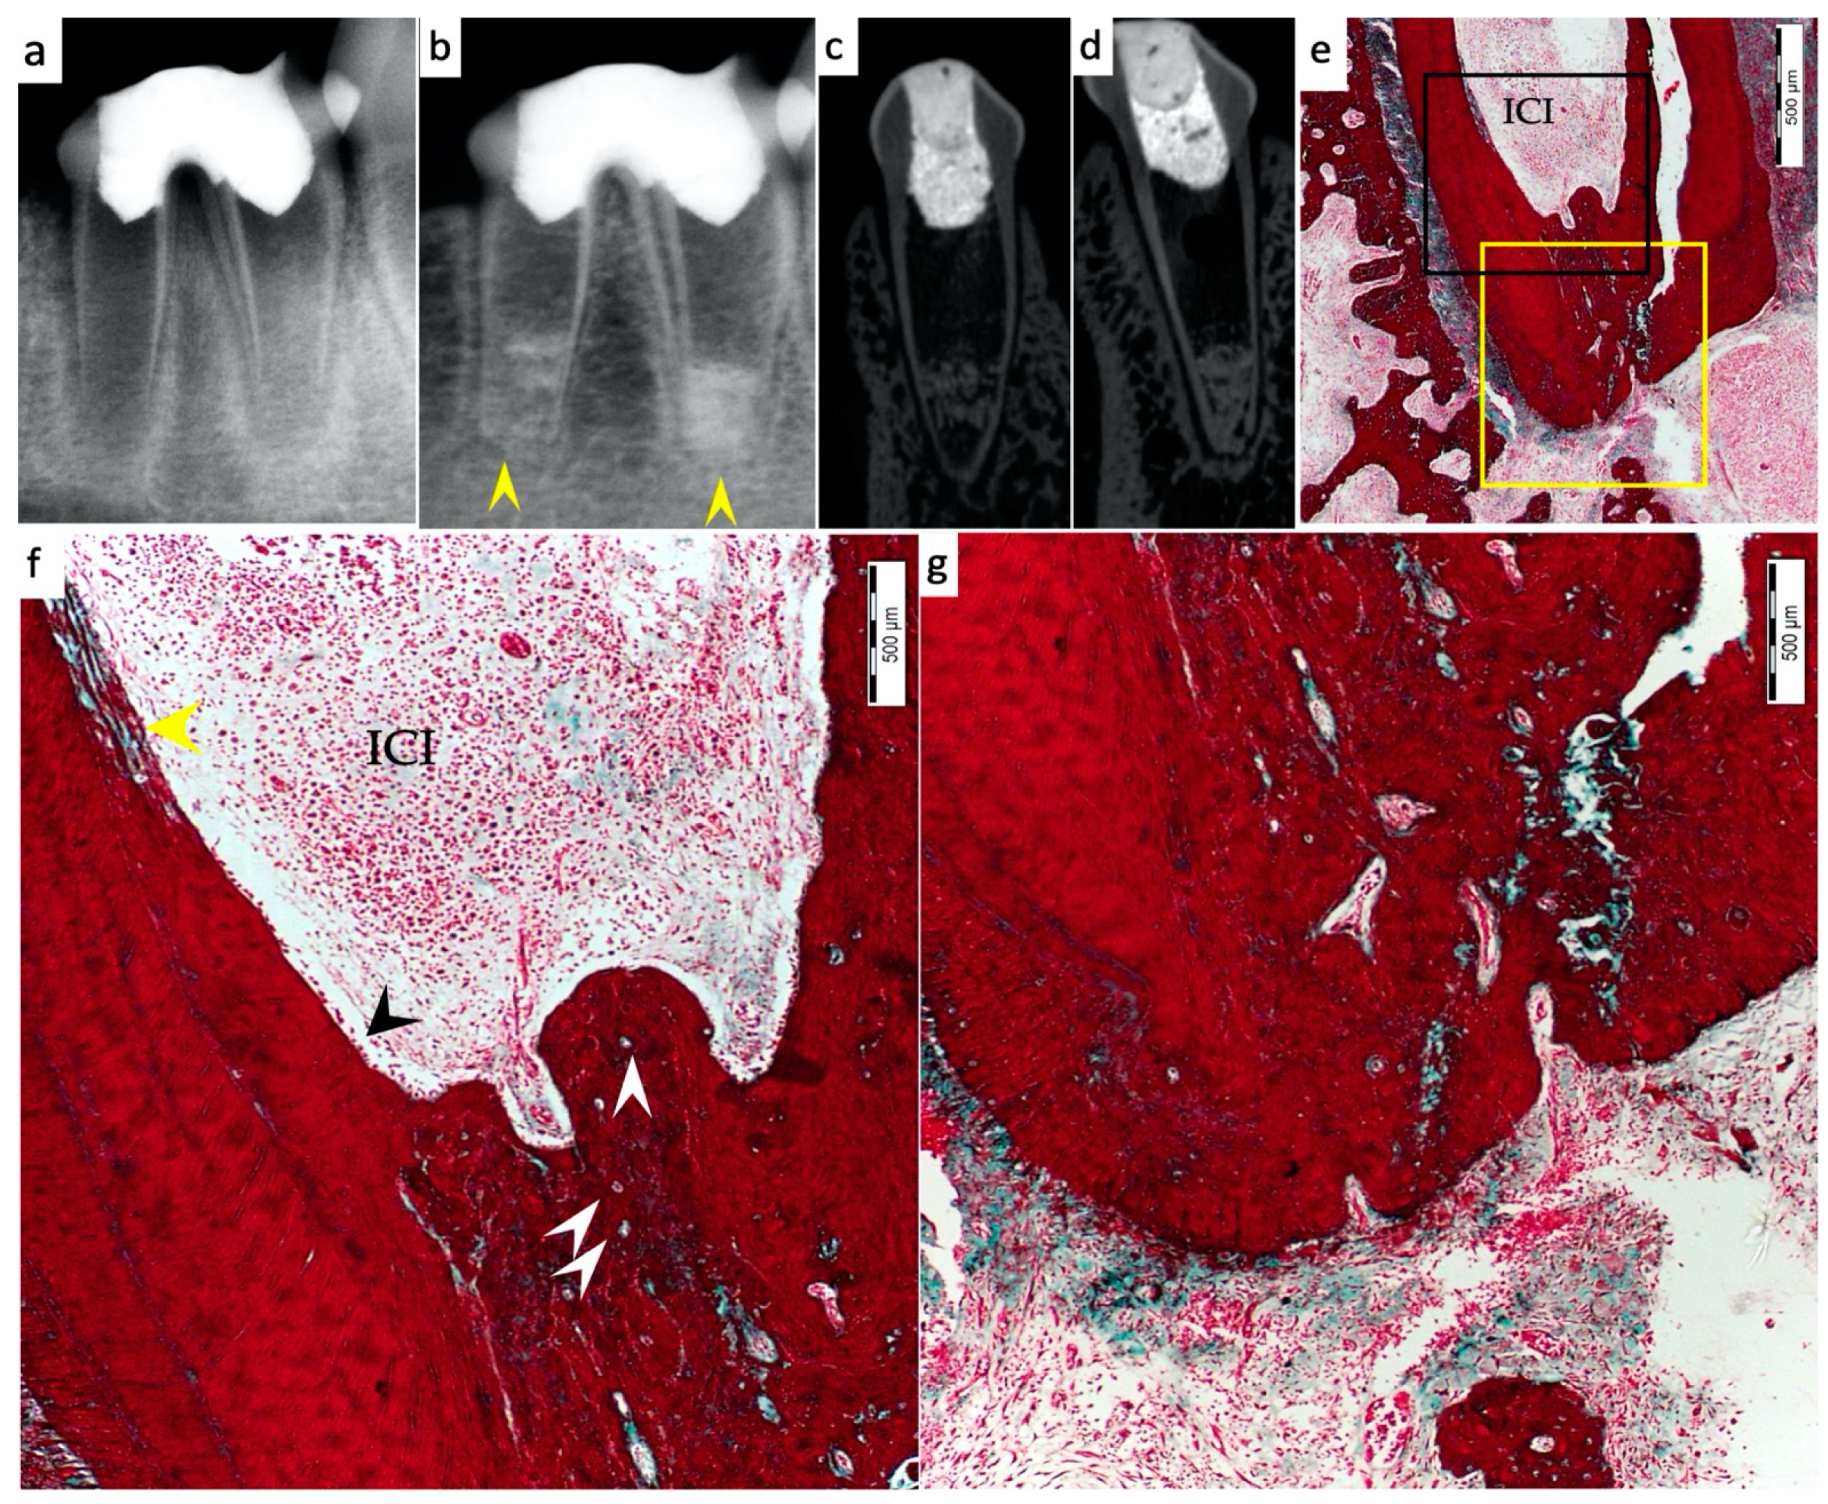

3.1. Hard Tissue Deposition

3.2. Type of Hard Tissue Formed

3.3. Vascularization and Formation of Vascularized Soft Connective Tissue

3.4. Degree of Inflammation

3.5. Apical Closure

3.6. Positive and Negative Control Groups